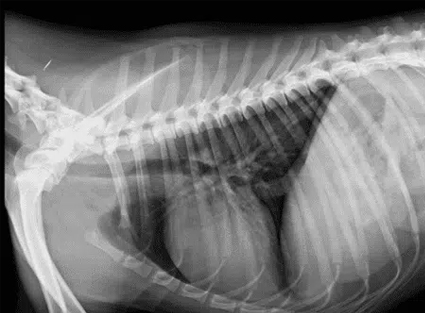

Radiología Torácica

- Evaluación de enfermedades pulmonares

- Diagnóstico de infecciones respiratorias

- Identificación de masas o tumores

- Evaluación cardíaca básica